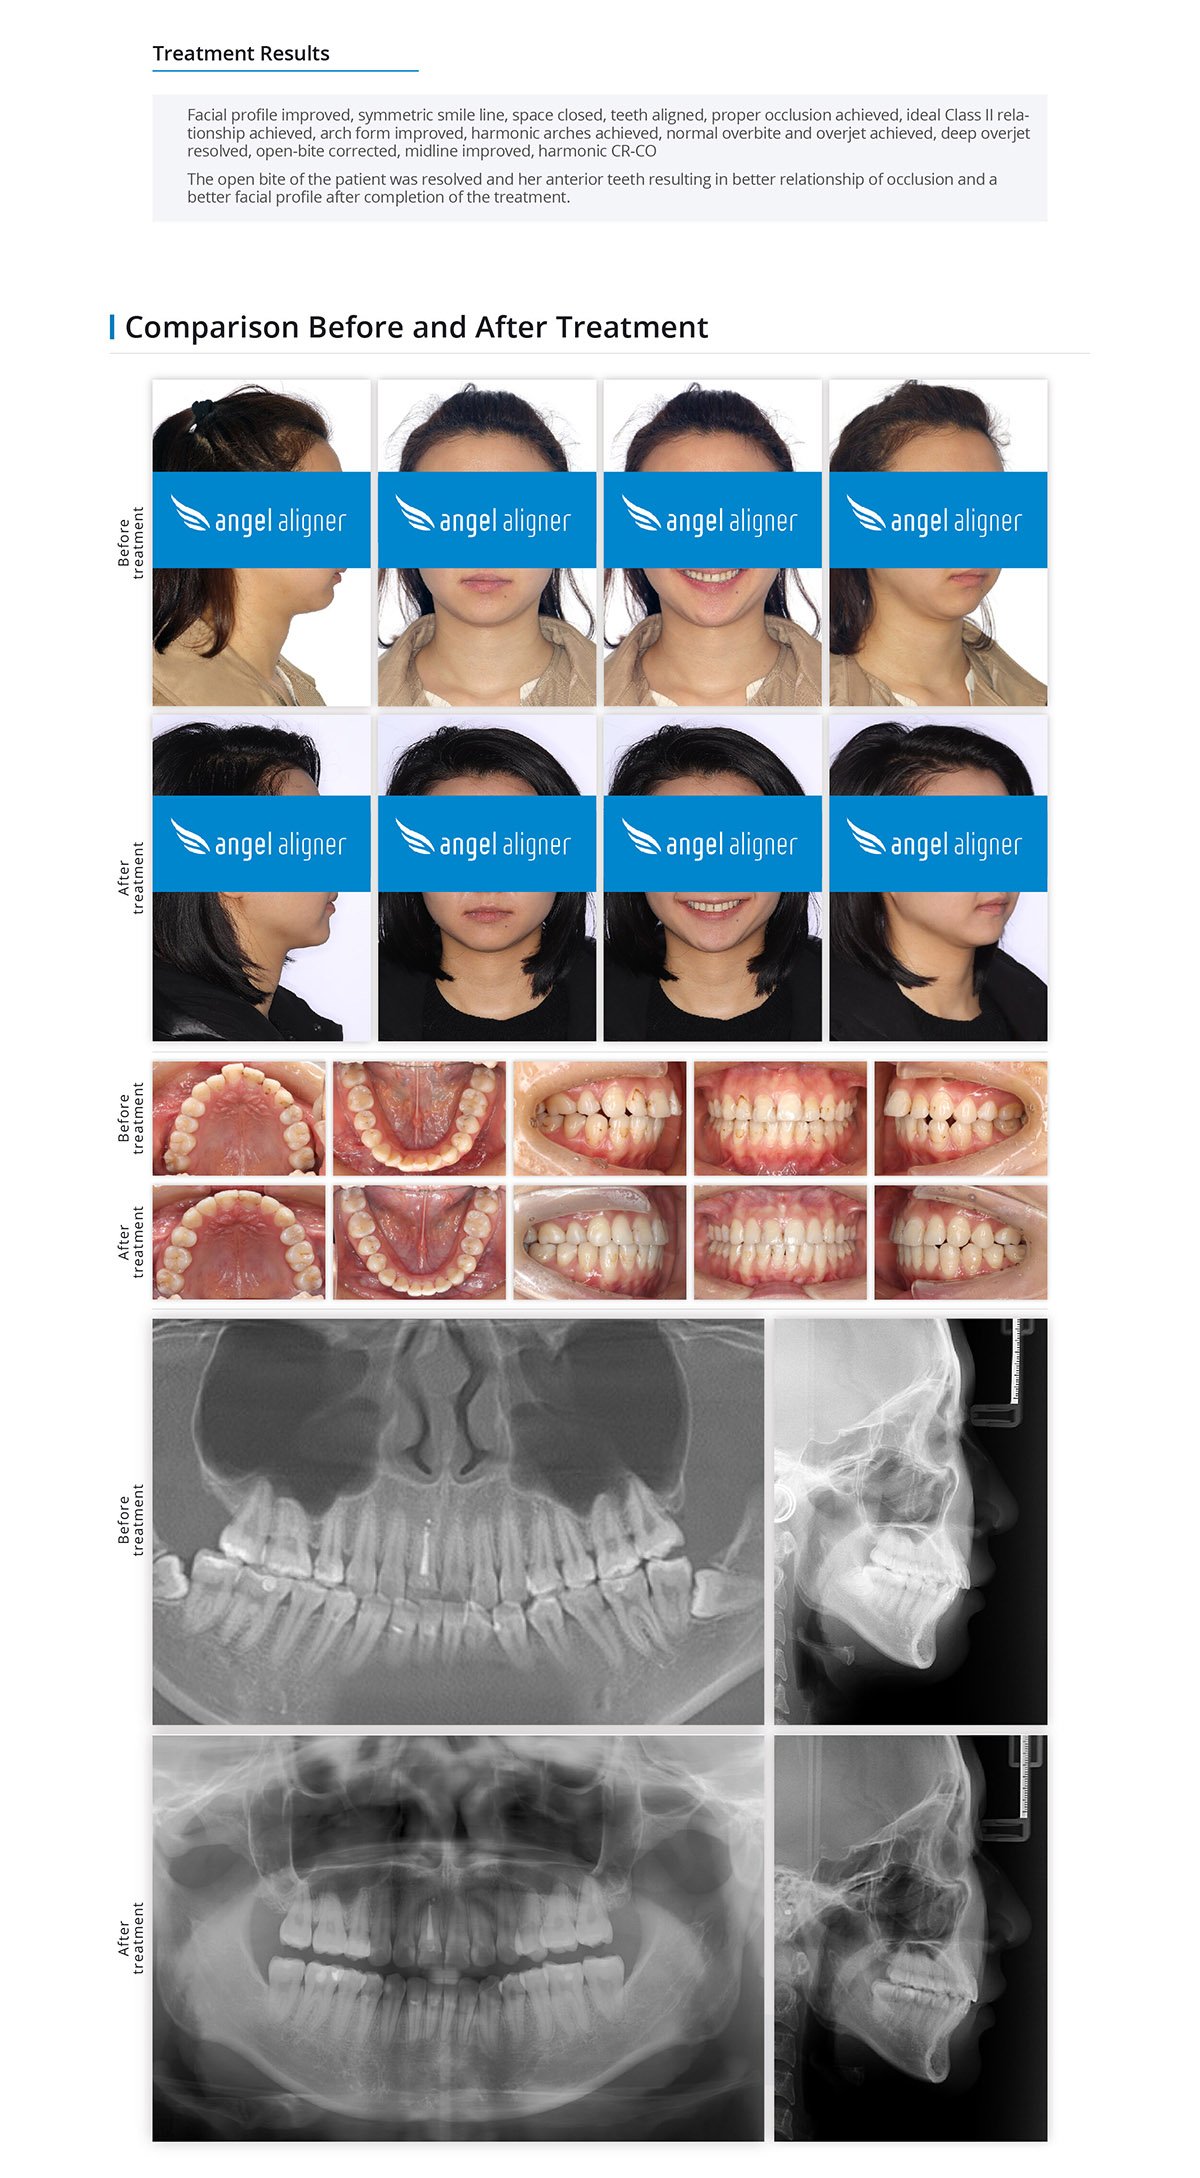

Treatment Of Anterior Tooth Severe Open-bite By Posterior Tooth Distalization And Intrusion With The Invisible Orthodontic Appliance

Female, 18 years old

Permanent dentition

Angel Aligner Pro

Total treatment time: 23 months